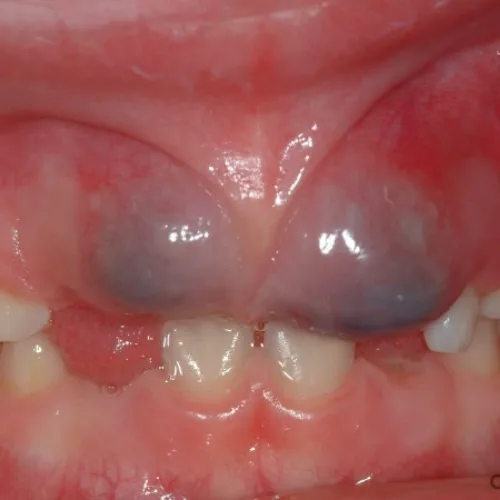

What Does an Eruption Cyst Look Like?

An eruption cyst is typically bluish-purple. It might appear reddish-brown if the fluid in the sac mixes with blood.

It’s typically a translucent dome of soft tissue that overlays an erupting tooth. It may also appear as a lesion or bruise.

Medical Image of an Eruption Cyst